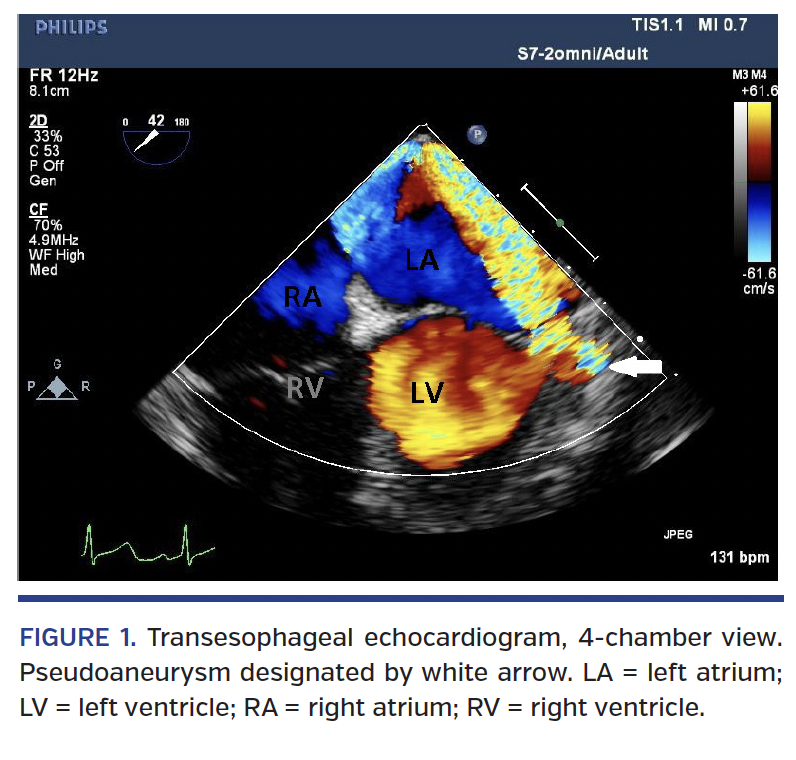

On hospital day 5, the patient developed hypotension requiring vasopressors. A repeat TTE revealed a moderate pericardial effusion and increased MR with an unusual eccentric jet. Subsequent transesophageal echocardiogram demonstrated a possible pseudoaneurysm at the base of the posterior leaflet of the mitral valve with new moderate MR (Figure 1). She underwent left and right heart catheterization with hemodynamic data consistent with pericardial tamponade. Left ventricular angiogram showed a possible pseudoaneurysm at the base of the anterolateral wall (Figure 2; Video 1). Pericardiocentesis was performed, revealing 300 mL of dark sanguineous fluid and resulting in hemodynamic improvement. Subsequent cardiac computed tomography angiogram demonstrated 13 mm pseudoaneurysm of the posterolateral wall just below the mitral annulus, with a 5 mm neck (Figure 3).